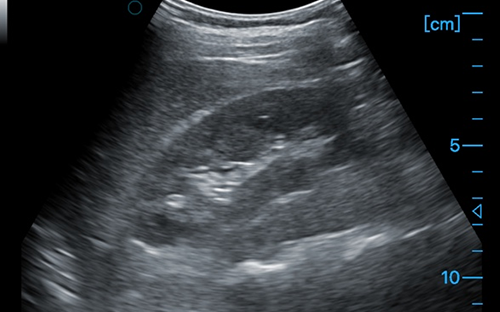

Kidney

Kidney